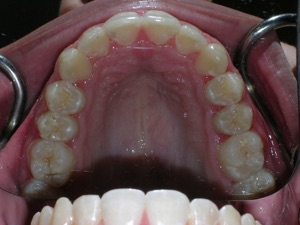

In this case, a young woman came to us with a desire to straighten her teeth. We elected to do Invisalign treatment with some enamel reduction and some dental arch expansion. Take a look...

Here she is on the day of appliance removal. You can see how the crossbite on the right has improved, as well as the lower front teeth crowding. Note that we elected to leave the lower second premolar in it’s rotated form.